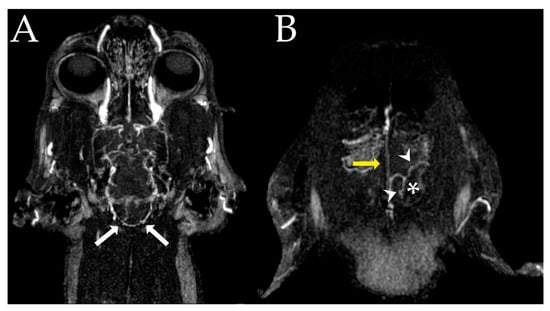

2.2. Images